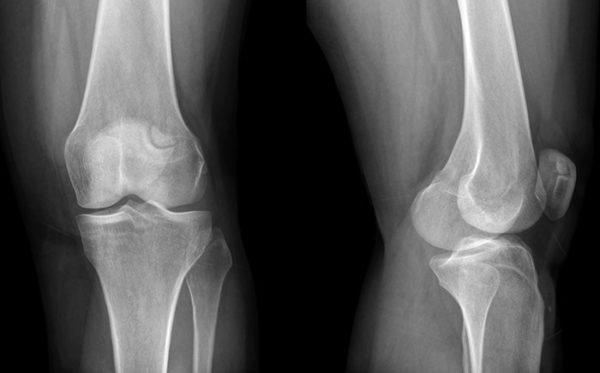

Артроз

Это разрушение внутрисуставного хряща колена и образования остеофитов, костных наростов. Артроз вызывает деформацию, сужение внутрисуставной щели и образованию анкилоза. Постепенно, без должного лечения, щель между суставами полностью исчезает, и он утрачивает свою подвижность.

Артрозом могут страдать люди в любом возрасте. На начальном этапе болезнь протекает незаметно, человек испытывает боль только после существенных нагрузок, которая затем сама проходит.

На второй стадии болевые ощущения начинают сопровождать человека ежедневно, возникает необходимость в приеме обезболивающих и противовоспалительных средств. Из-за боли амплитуда движений в колене уменьшается.

На последнем этапе происходит полное разрушение хрящевой ткани. Больной страдает постоянными болями, теряет способность к передвижению, помочь в данной ситуации может только операция.